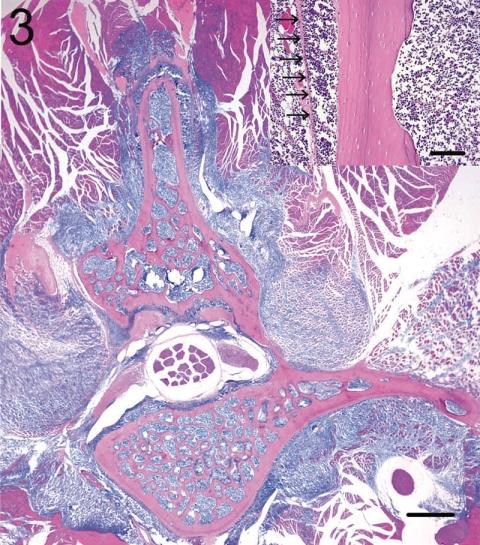

Although spontaneously occurring neoplasms have been reported repeatedly in F344, SD and Wistar rats, which are commonly used strains for routine toxicologic and carcinogenicity studies, there are only a few reports of malignant lymphoma or lymphatic leukemia except for large granular lymphocytic leukemia (LGL) in F344 rats. Malignant lymphoma (lymphosarcoma) is thought to be uncommon in F344 rats. The authors encountered malignant lymphomas of the non-LGL leukemia type with characteristic pathologic features in WBN/Kob rats. The mean age at onset of the disease in all 13 affected rats (8 males and 5 females) was about 60 weeks. Common and characteristic clinical signs were abnormal gait with hind limb paralysis. Macroscopically, the enlargement of the lymph nodes, spleen and liver was slight to moderate. Scattered multiple white-to-gray nodules encompassed the aorta and assumed a bead-like appearance near the thoracic and lumbar vertebrae. Histopathologically, neoplastic proliferative changes were predominant in the bone marrow tissue of the entire body, and many tumor cells infiltrated the spleen and several lymph nodes. The most striking histological features were constant and severe infiltration of tumor cells in the adipose tissue and skeletal muscle adjacent the thoracic and lumber vertebrae. Immunohistochemically, all tumor cells were positive for B-cell markers (PAX-5, CD79a and CD45) and negative for CD3. From the results of immunohistochemistry and morphological examination, these tumors were diagnosed as malignant B-cell lymphomas.

尽管在常用于常规毒理学和致癌性研究的F344、SD和Wistar大鼠中反复报道过自发发生的肿瘤,但除了F344大鼠中的大颗粒淋巴细胞白血病(LGL)外,关于恶性淋巴瘤或淋巴白血病的报道很少。恶性淋巴瘤(淋巴肉瘤)在F344大鼠中被认为不常见。作者在WBN/Kob大鼠中遇到了具有特征性病理特征的非LGL白血病类型的恶性淋巴瘤。所有13只患病大鼠(8只雄性和5只雌性)的疾病发病平均年龄约为60周。常见且特征性的临床症状是伴有后肢麻痹的异常步态。宏观上,淋巴结、脾脏和肝脏的肿大为轻度至中度。散在的多个白色至灰色结节围绕主动脉,在胸椎和腰椎附近呈串珠状外观。组织病理学上,肿瘤性增殖变化在全身骨髓组织中占主导,许多肿瘤细胞浸润脾脏和多个淋巴结。最显著的组织学特征是肿瘤细胞持续且严重浸润胸椎和腰椎附近的脂肪组织和骨骼肌。免疫组化显示,所有肿瘤细胞B细胞标志物(PAX-5、CD79a和CD45)呈阳性,CD3呈阴性。根据免疫组化和形态学检查结果,这些肿瘤被诊断为恶性B细胞淋巴瘤。